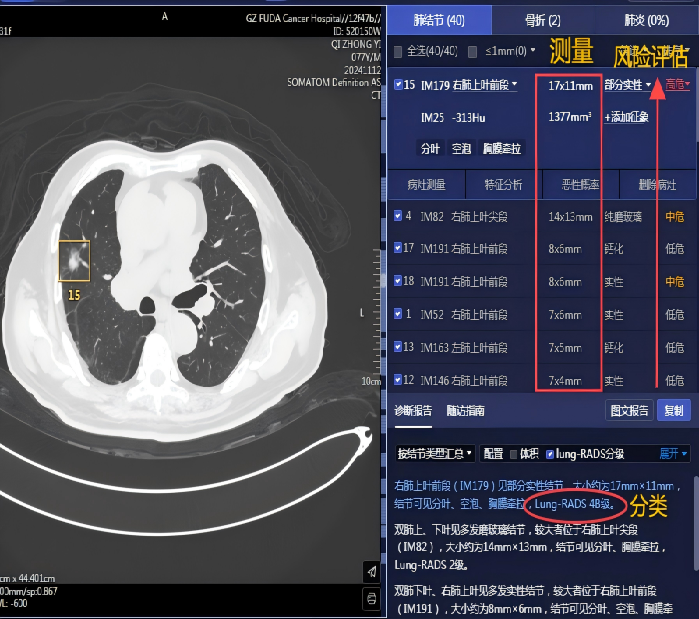

在發(fā)現(xiàn)疑似病灶后,系統(tǒng)會自動快速定位可疑病灶區(qū)域,用色框清晰標注小結節(jié)坐標提示醫(yī)生,并對結節(jié)的可疑病灶數(shù)、性質(zhì)、直徑、體積、CT值等信息以及影像學表現(xiàn)進行描述,醫(yī)生就可以對這些有問題的地方著重處理,為后續(xù)治療方案的制定提供了關鍵依據(jù)。

03 鑒別良惡,精準診斷

憑借強大的數(shù)據(jù)分析能力,AI可以深度剖析結節(jié)的各種特征,并結合豐富的臨床信息,在良惡性鑒別診斷上表現(xiàn)卓越。如:快速給出良惡性判斷及其惡性風險分級,提高診斷效率的同時,還能突顯結節(jié)圖像中的可疑征象,并實時呈現(xiàn)給臨床醫(yī)生,為結節(jié)的分類診斷提供重要參考依據(jù),從而有利于降低誤診率,避免了患者不必要的擔憂和過度治療。

▲患者77歲,男,右下肺切除術后12年余,發(fā)現(xiàn)右上肺結節(jié)2年余;直腸癌、膀胱癌綜合治療后。完善相關檢查AI提示右上肺結節(jié)為高危,結合既往病史,我院為其施行右肺結節(jié)經(jīng)皮穿刺細胞學涂片+冷凍消融術,右肺結節(jié)細胞學檢查示:送檢(右肺)細針穿刺細胞學涂片中查見癌細胞。